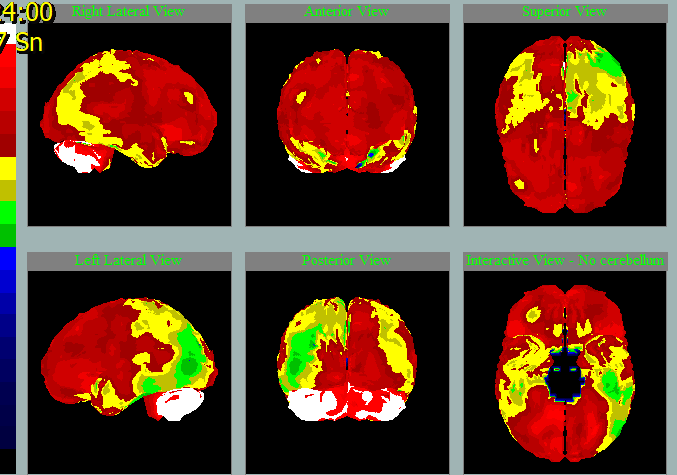

Takto na SPECT mozku zpracovaném NeuroGamem vypadá:

Perfúze při neurodegenerativním onemocnění mozku